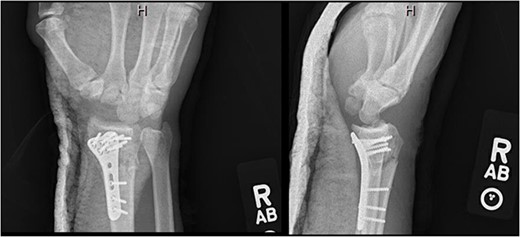

At 3-month postoperative follow-up, grip strength was 18 lbs on the right and 25 lbs on the left. Pinch strength was 9 lbs on the left and 7 lbs on the right. At 5-month follow-up, the patient was transporting himself using a wheelchair, and his wrist pain was well controlled. At 7-month follow-up, grip strength was improved to 30 lbs on the right and 45 lbs on the left; pinch strength was 3 lbs on the right and 8 lbs on the left. Right wrist motion demonstrated 40° of flexion, 20° of extension, and full unlimited pronosupination. Radiographs demonstrated a healed distal radius fracture with no signs of arthrosis at the new radiocarpal joint (Fig. 4). At 1-year follow-up, the patient continued to progress functionally with no new complaints of pain. At 2-year follow up, the patient’s Disabilities of the Arm, Shoulder, and Hand score was 35.83.

AP and lateral views at 7-month follow-up demonstrating a healed right distal radius fracture without arthrosis at the new radiocarpal joint.